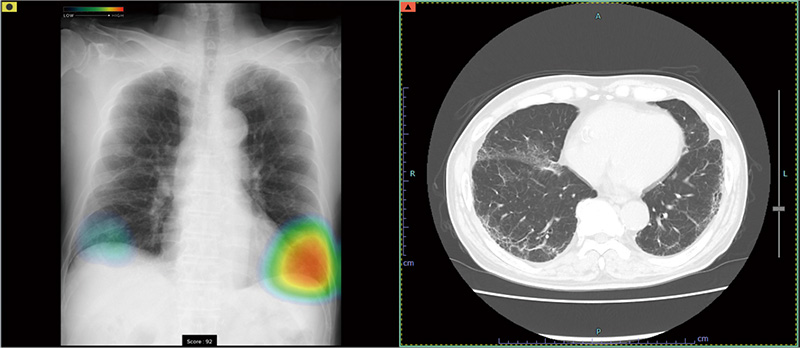

症例別ヒートマップとCTの例

当院では、富士フイルム社製の最新AI技術を搭載した画像診断ワークステーション「CarnaCore(カルナコア)」を導入しています。

このシステムでは、AIが撮影画像を瞬時に解析します。肺がんの疑いがある結節、肺炎、気胸といった見落としがちな微細なサインを自動検出し、医師の診断を強力にバックアップします。

医師による確かな読影に、客観的なAI解析を組み合わせることで、病変の早期発見と診断精度の向上に努め、より安心で効率的な診療体制を提供いたします。

• 高精度な解析: AI技術(Deep Learning)が医師の画像診断を強力にバックアップ。